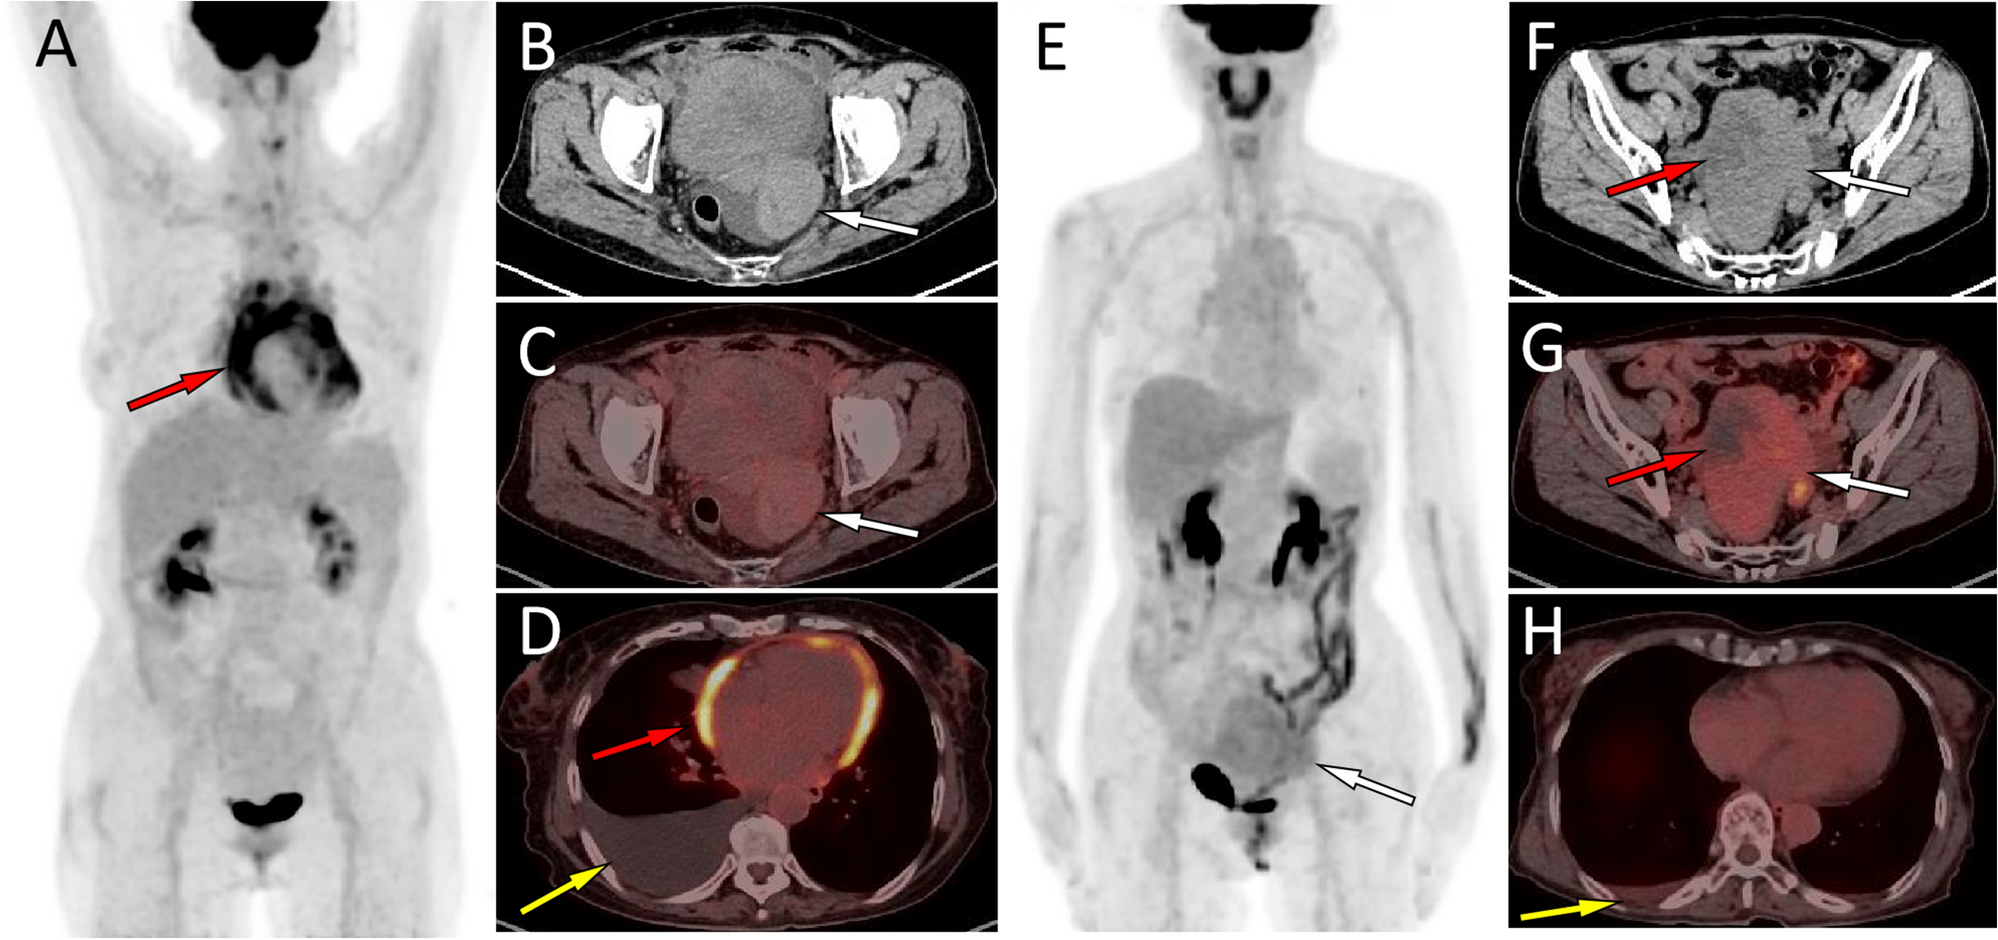

Figure 2

(A–D) Representative 18F-FDG PET/CT images of theca fibroma in a 72-year-old woman who sought medical help for two weeks because of pain in the precordial area and difficulty breathing. The maximum intensity projection (MIP, A) showed no significant increase in 18F-FDG uptake in the rest of the body except in the pericardial area (red arrow). Axial CT (B, arrow) showed a mass of first order soft tissue density on the left side of the pelvic cavity, and no significant uptake of 18F-FDG was observed on the corresponding PET/CT fusion (C, arrow). Axial PET/CT reveals that the lesions shown on the MIP map are pericardial effusions with increased diffuse uptake of 18F-FDG (D, red arrow). In addition, an intermediate pleural effusion without increased uptake of 18F-FDG was seen in the right thoracic cavity (D, yellow arrow). (E–H) Representative 18F-FDG PET/CT images of granulosa cell tumor (adults type) in a 45-year-old woman who sought medical attention for one month due to right chest pain. The MIP map shows a shadow with slightly increased 18F-FDG uptake in the lower abdomen (E, arrow). Axial CT (F) showed that the lesion was a soft tissue mass (white arrow) with low density cystic degeneration (red arrow) in the pelvic cavity. The axial PET/CT (G) of the corresponding site showed a mild increase in 18F-FDG uptake in the solid part (white arrow) of the tumor, with a SUVmax of 2.4, while no radioactive uptake was observed in the cystic area (red arrow). Axial PET/CT at the chest level showed a small amount of fluid in the right thoracic cavity without radioactive uptake (H, yellow arrow), and the amount of fluid accumulation is significantly lower than the amount of fluid accumulation in the serous cavity caused by serous cavity effusion.